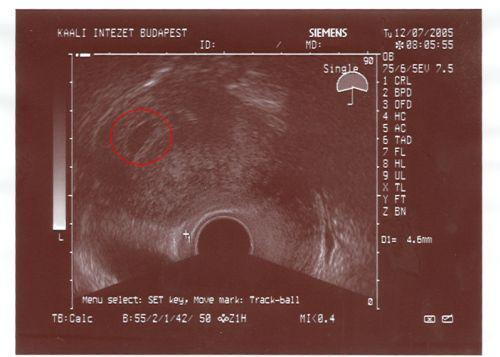

Anyukádat nagyon sajnálom, átérzem a helyzetetdet. De engedd el most már őt is a méhen kívüli terhesség gondolatát és lehetőségét. Nem lesz baj. Remélejük, hogy most sikerült az inszem, és egy gyönyörű kis petezsák lesz majd az UH-n, ha mész a dokihoz, vagy egy jó kis HCG érték. Akkor pedig nem kell félned a lombiktól.